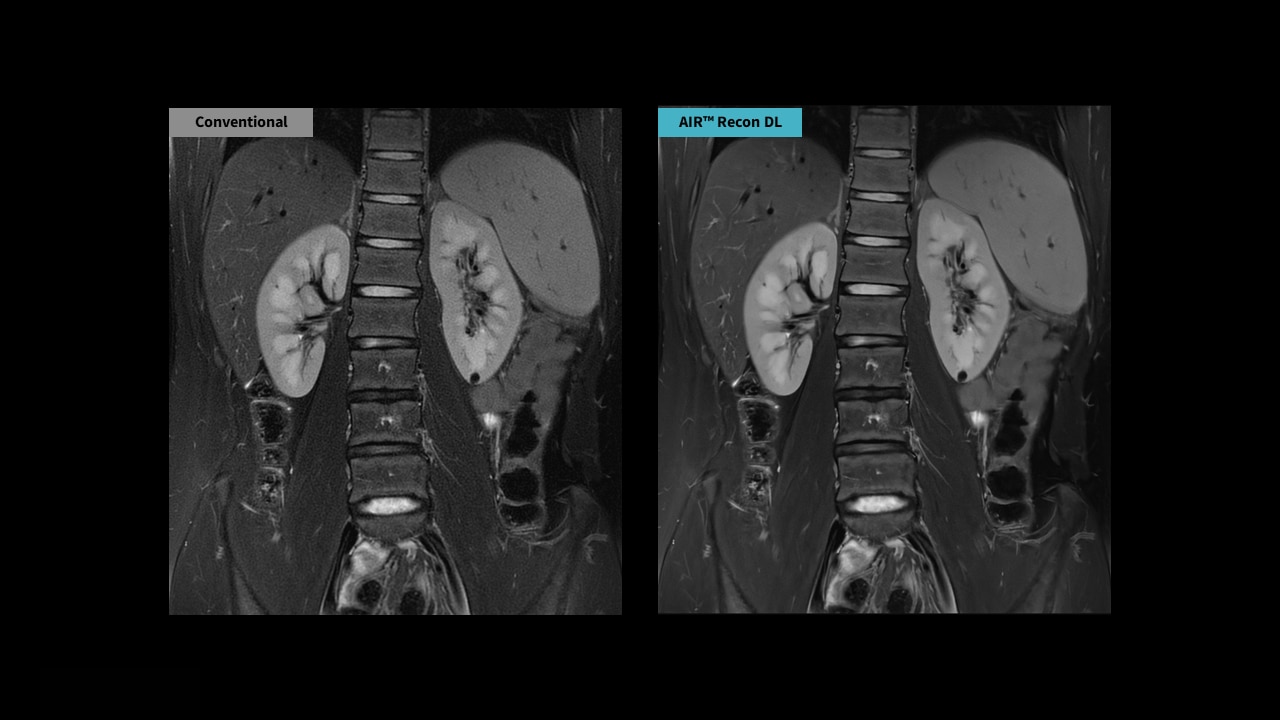

PROPELLER is compatible with AIR™ Recon DL, GE HealthCare's a pioneering deep-learning-based reconstruction algorithm that enables radiologists to achieve pin-sharp images quicker.